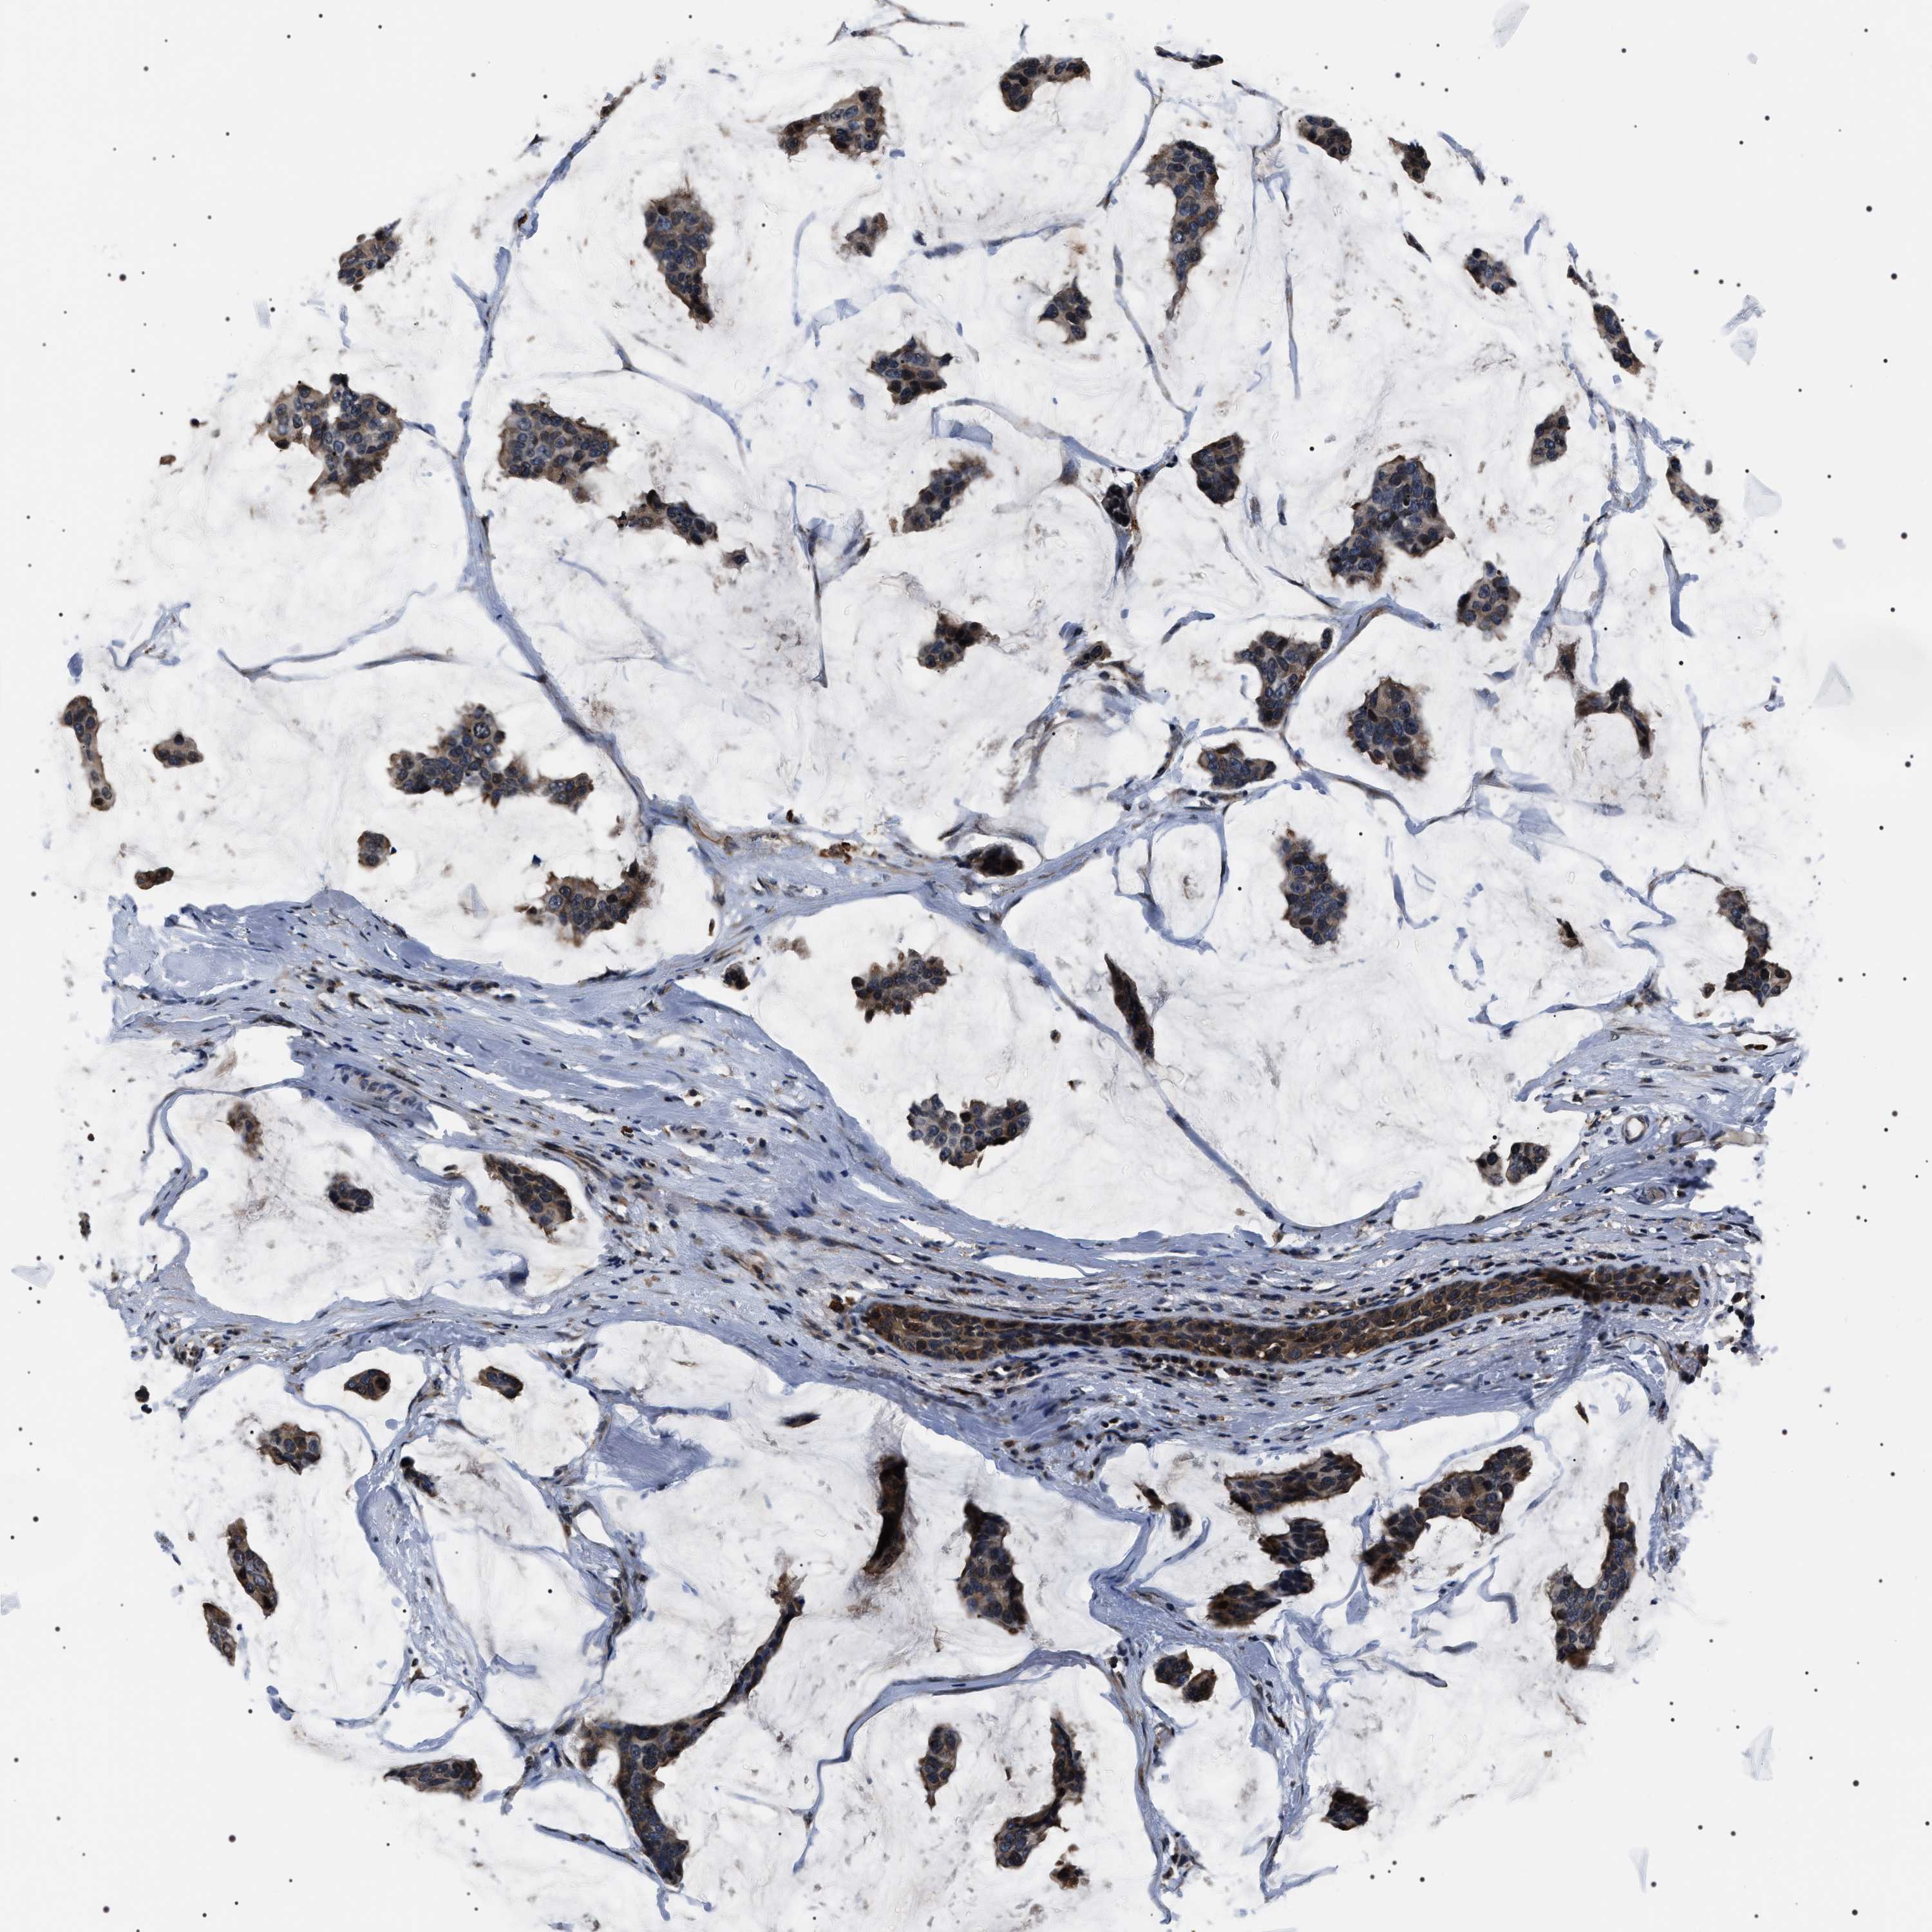

CANCER BREAST CANCER Show tissue menu

BRCA TCGA BRCA VALIDATION PROTEIN EXPRESSION